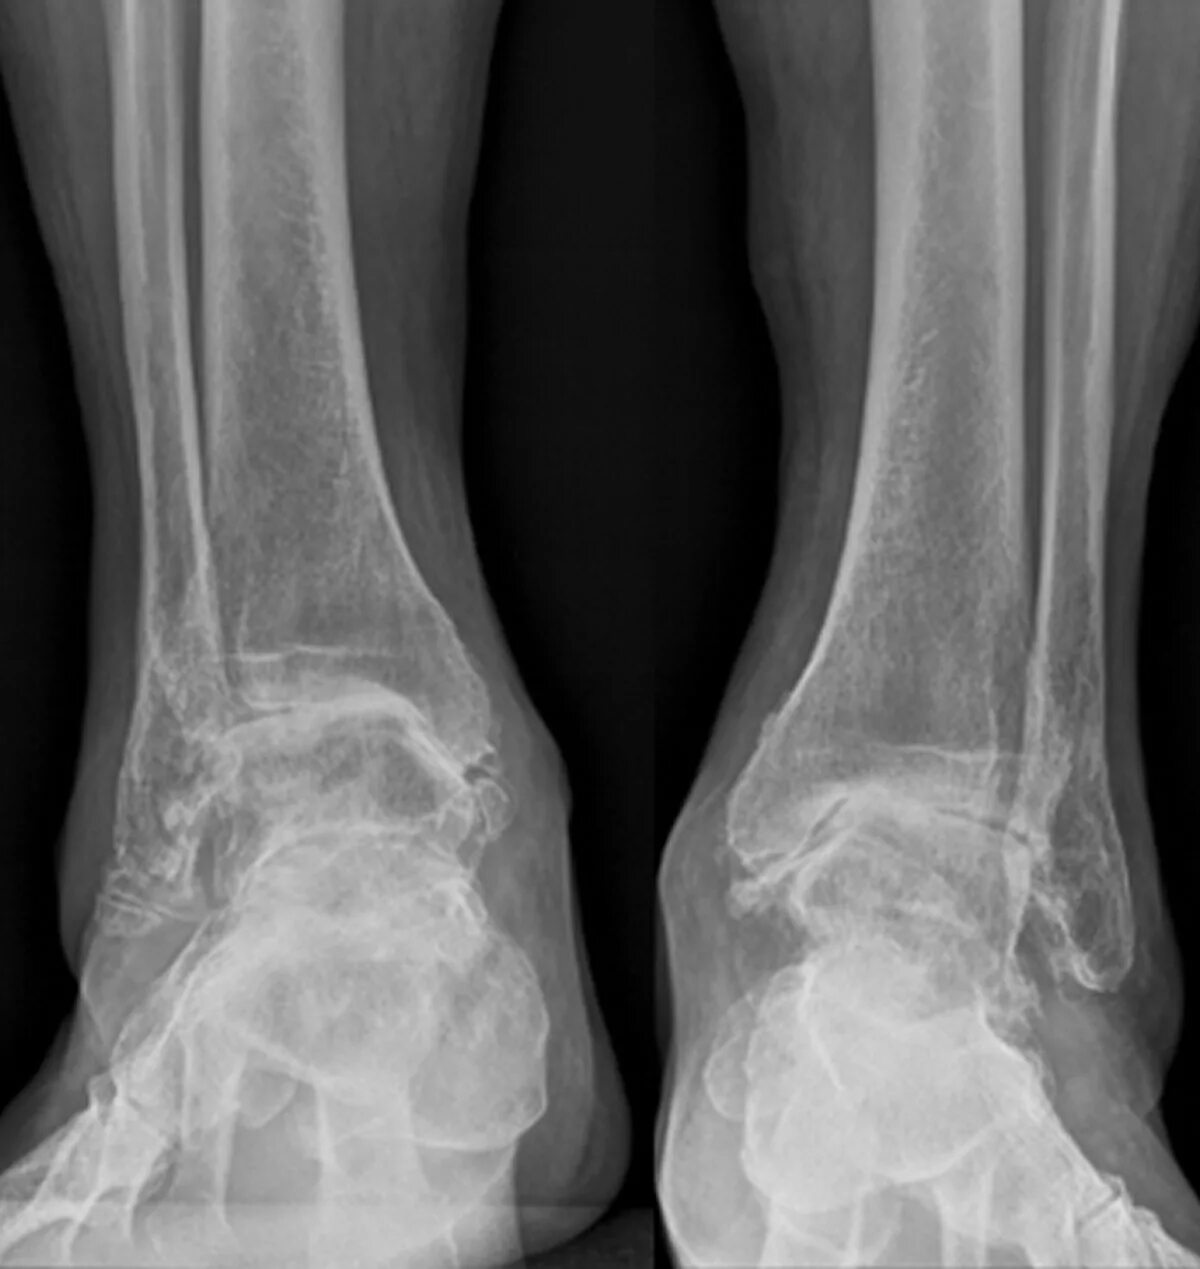

Артроз голеностопного сустава код